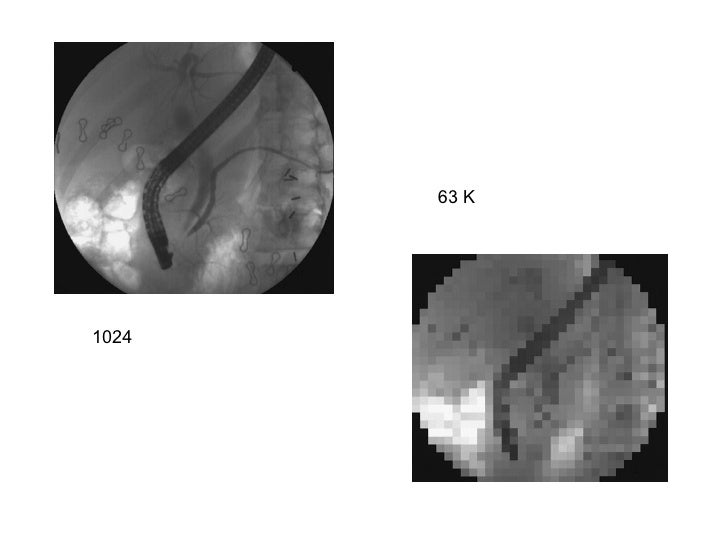

images of the matrix smallest which has size pixels Digital fluoro high quality jpeg wallpaper download

images of has matrix which the size smallest pixels fluoro Digital high quality jpeg wallpaper download

images of the matrix smallest which has size pixels Digital fluoro high quality jpeg wallpaper download

images of has matrix which the size smallest pixels fluoro Digital high quality jpeg wallpaper download